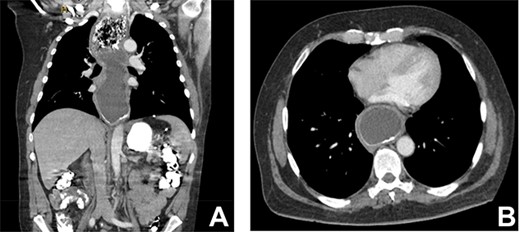

(A) CT coronal image of chest and abdomen demonstrating megaoesophagus secondary to the LAGB; (B) CT axial image of chest demonstrating megaoesophagus causing left atrial compression.

Three months after band removal, the patient reported complete resolution of his symptoms. Repeat gastroscopy demonstrated oesophageal mucosal healing and no residual hiatal hernia. TTE showed that left atrium was moderately enlarged (but to a lesser extent compared to previous study) and normal left and right ventricular systolic function and dimensions with estimated left ventricular ejection fraction of 60%. Furthermore, the post-operative Barium swallow study (Fig. 4) demonstrated a 6.7-cm oesophageal dilatation and dysmotility. There was no significant delay in passage of barium into a non-distended stomach. Since band removal his weight had increased by 17 kg (112.8 kg, BMI: 36.4). Further discussions with the patient led to laparoscopic sleeve gastrectomy a month later (Fig. 5).

In the case of this patient, the extent of his megaesophagus resulted in significant compression of the left atrium observed on TTE and CT, which fortunately did not cause haemodynamic compromise or obvious and clinically evident intracardiac thrombus. To our knowledge, compression of the cardiac chambers by oesophageal dilatation is an extremely rare complication of LAGB. A systematic literature review of megaoesophagus in LAGB patients was performed (Table 1).